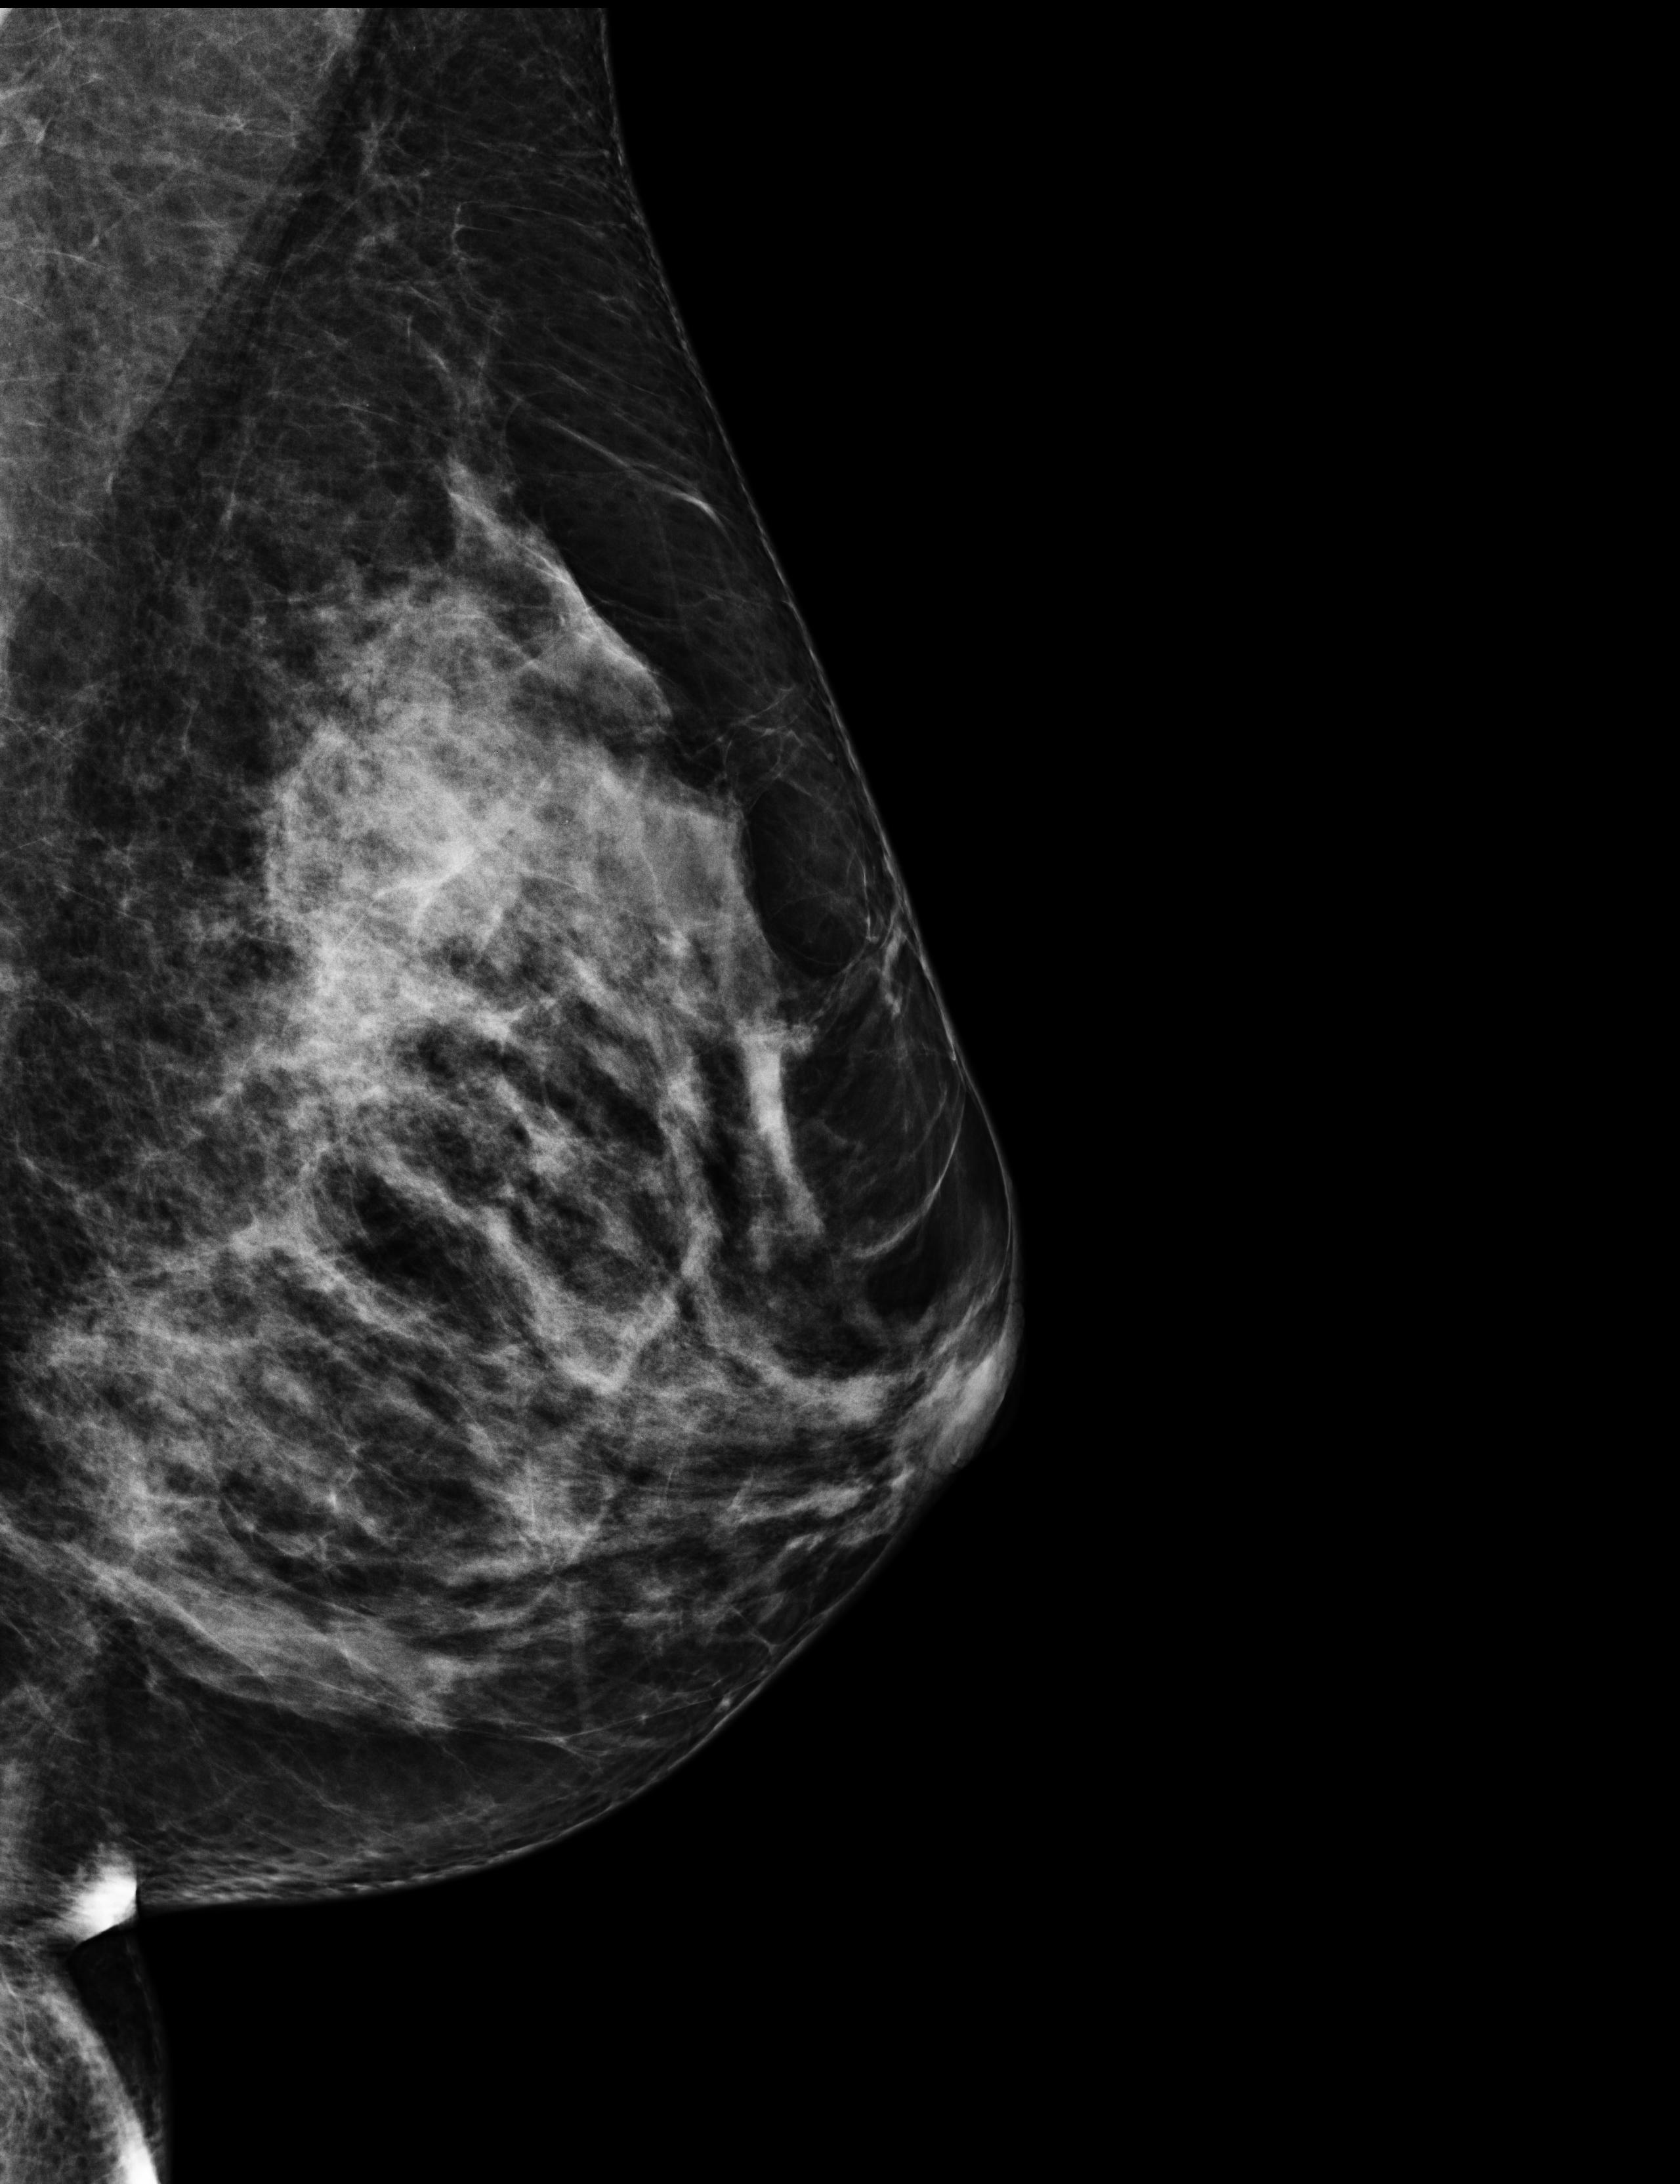

The radiologist that saw me on October 17th, booked me a mammography for 3 days later. I had never done this exam before, and it was very painful, especially because my breast was still suffering from the biopsy. But a mammography can highlight things that an echography cannot, so it was necessary. In the meantime, the results of my biopsy came in, and there was no doubt: “it’s cancer, a breast carcinoma, and unfortunately a triple negative one”, said the doctor.

The data I chose for this event are the four scans of the mammography and a revised version of the biopsy results. The biopsy analysis started on 2023-10-17 at 5:50pm, and it kept being updated until 2023-11-01. I have highlighted in red the medical decisions. At the end you’ll also find a single value, the level of the CA 15-3 tumor marker in my blood. It will come back quite a bit in the following months.